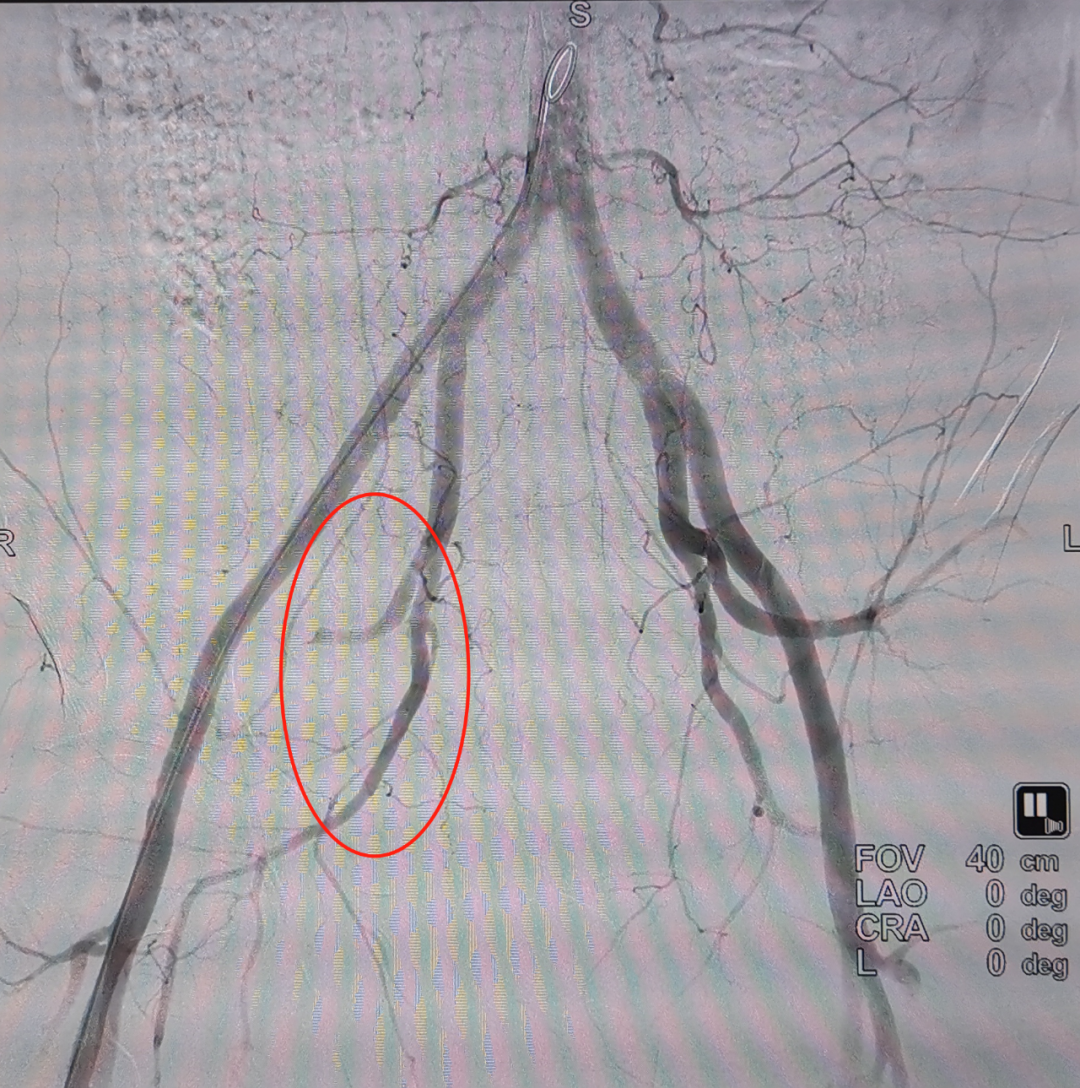

快速分析各項(xiàng)檢查結(jié)果:復(fù)雜的雙側(cè)骨盆開放性粉碎性骨折+髂內(nèi)動(dòng)脈斷裂+尿道斷裂+雙側(cè)多發(fā)肋骨骨折+雙側(cè)血?dú)庑?嚴(yán)重肺挫傷+腹部閉合性損傷+皮下大面積脫套傷+多處血腫等,出血迅猛,病情十分危急。曹飛主任、周春峰主任、介入科孫英豪主任一致認(rèn)為病情非常危急,需立即對患者進(jìn)行手術(shù),即緊急損傷控制性手術(shù)DCS(介入血管造影+栓塞+骨盆外固定+膀胱造瘺術(shù)),止血、糾正休克及控制傷情進(jìn)一步惡化。

第一次手術(shù)~

第一次栓塞成功~

參與急救的醫(yī)護(hù)人員都長長地舒了一口氣,順利完成搶救的第一步。在創(chuàng)傷中心有“黃金1小時(shí)”的理念,即嚴(yán)重創(chuàng)傷患者受傷后1小時(shí)是救治的關(guān)鍵時(shí)期。對于嚴(yán)重創(chuàng)傷的病人來說,時(shí)間就是生命,搶救就是和時(shí)間賽跑,需要爭分奪秒。能否在“黃金期”內(nèi)得到準(zhǔn)確的診斷與治療,往往顯著降低創(chuàng)傷死亡三聯(lián)征的發(fā)生(低體溫、酸中毒、凝血?。瑥亩绊懮媛?。

各學(xué)科專家立即趕到ICU第二輪全院MDT,快速討論考慮為再出血,決定行介入手術(shù)擴(kuò)大栓塞范圍,繼續(xù)大量輸血(MTP)方案。1個(gè)多小時(shí)后,隨著二次介入手術(shù)順利完成,患者的情況恢復(fù)穩(wěn)定。